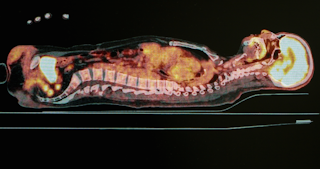

tomografia de emissão positrão(PET)

as técnicas de imagiologia utilizadas com raios-x, CT e MRI, são principalmente concebidas para observar informação estrutural – isto inclui o arranjo anatómico e a localização de doenças ou lesões. A imagem PET é um processo único de imagem, uma vez que pode identificar e Imagem informações funcionais tais como metabólicas (a conversão de energia) ou processos químicos de órgãos internos do corpo.

para isso, substâncias radioativas precisam ser injetadas em pacientes e estas são quimicamente ligadas a compostos usados por nossos órgãos (como glicose) ou moléculas que se ligam a receptores específicos ou tipos específicos de células (como proteínas).

estas substâncias radioactivas emitem raios gama (outra forma de radiação ionizante). A partir de sua localização dentro do corpo, os raios gama passam através do tecido e sair do corpo onde eles são detectados por um scanner PET contendo uma câmera gama, enquanto o paciente está deitado ainda.

o scanner PET detecta os raios gama, converte sua intensidade ou força em um sinal elétrico e, em seguida, reconstruir uma imagem baseada nesta intensidade. Os detectores são dispostos em torno do corpo de um paciente para que a localização de origem dos raios gama dentro do paciente pode ser calculada usando processos matemáticos.A imagem PET é excelente para identificar a actividade de tumores em órgãos que não podem ser estruturalmente identificados com outras técnicas de imagem.Técnicas de imagem semelhantes a este têm sido em torno de muitas décadas e técnicas de imagem PET são realizadas quase todos os dias em grandes hospitais em toda a Austrália.